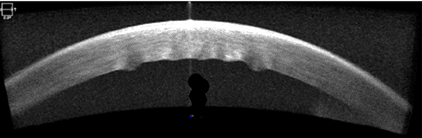

The patient did not return until six weeks later and reported that her vision became clear a week before. Her corrected visual acuity was 20/20 OD and OS. The intraocular pressure was 14 mmHg OD and 13 mmHg OS with Goldmann tonometry. The anterior segment was unremarkable, with no corneal edema, folds, or superficial punctate keratitis OU (Figures 4 and 5). Corneal pachymetry revealed central corneal thicknesses of 509um OD and 507um OS. The bilateral corneal edema had resolved.